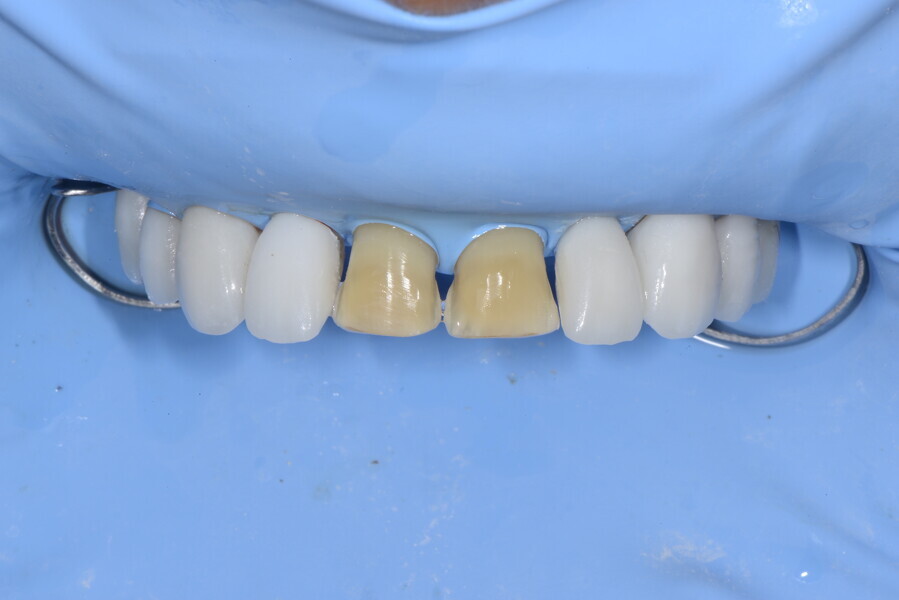

The 58-year-old patient wished to improve his oral aesthetics and function, complaining of mobility of the posterior teeth and wear of the anterior teeth. After data collection, a very complex situation was identified (Figs. 11–13):

1. severe periodontitis with poor prognosis of some teeth;

2. anterior crossbite;

3. severe wear mainly of the anterior teeth and compensatory eruption;38

4. atypical swallowing and lower posture of the tongue at rest;

5. masticatory dysfunction during the mastication test; and

6. no significant signs of temporomandibular disorder.

During the first visit, we checked the centric relation with cotton rolls, eliminating the posterior mesialising precontact and then performed a direct composite aesthetic and functional mock-up in this new position, not only to motivate the patient regarding the final result but also to help him understand better overall why tongue therapy, tooth alignment and dental resurfacing for augmentation of the vertical dimension of occlusion were required (Figs. 14 & 15).